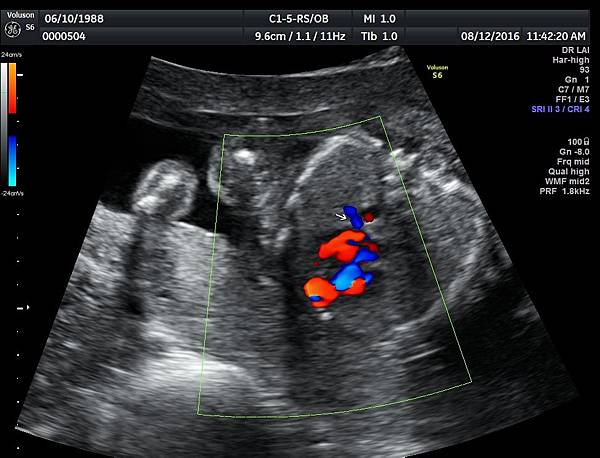

我看肺靜脈的心路歷程可以分成三個階段,第一個階段是用gray scale(黑白)看到左右肺靜脈下行支回到左心房(附圖 1.2.),第二個階段是用flow(彩色)看到左右肺靜脈回到左心房(附圖 3.4.),第三階段是同時要看到黑白和彩色的左右肺靜脈回到左心房,為什麼只有看flow(彩色)不安全呢?因為右肺靜脈的flow有時候是假影,為何會看到假影?因為右心房到左心房的flow overlapping(重疊)造成的(附圖 5.),如何判斷是假影,只要關掉flow看黑白的即可證明右肺靜脈沒有進入左心房(附圖 6.)。

如果同時看到左右肺靜脈進入左心房,這種誤判的機率下降很多,如果只能看到一條肺靜脈的血流,我會選擇左肺靜脈(附圖 7.8.),因為左肺靜脈的血流比較不會被overlapping,最安全的方法是黑白和彩色都看到左右肺靜脈進入左心房,只是需要胎兒姿勢配合,當然孕婦的體重也是需要考量的因素。